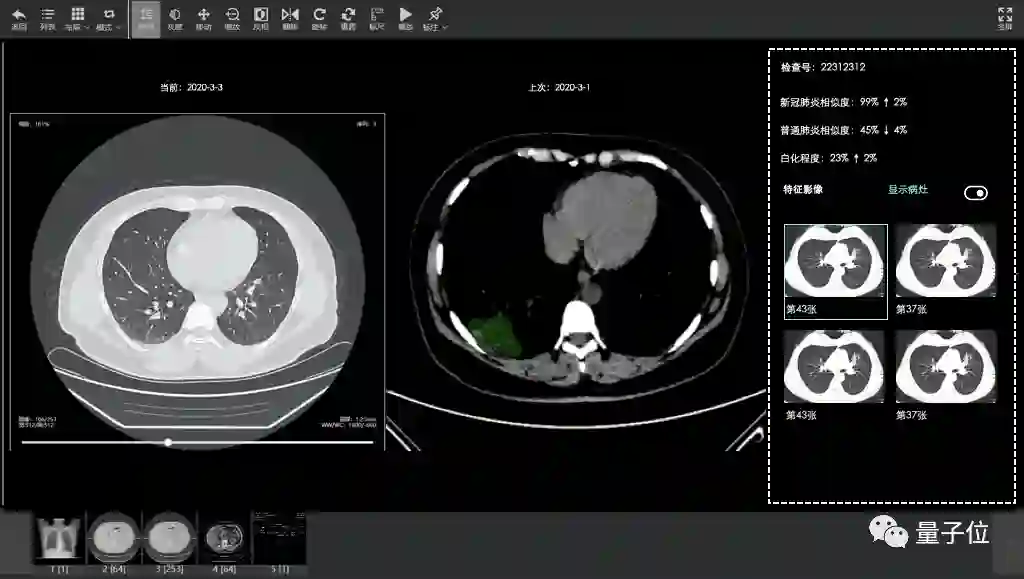

2月15日,达摩院医疗AI团队与合作伙伴一起,基于5000CT影像样本数据,快速研发出了CT影像算法,在郑州小汤山上线,可以在20秒内对新冠疑似患者CT影像做出判读,并量化病症的轻重程度,分析结果准确率达到96%。

至今这套AI系统已在浙江、河南、湖北、上海、广东、江苏、安徽等16个省市的170家医院落地,诊断超过34万临床病例。

而达摩院等医疗AI机构,就在这样的险峻形势中出手,联合伙伴打造的新冠病毒CT影响诊断系统,从上传数据到得到结果,诊断一个病例平均仅需20秒,计算时间最快仅2秒。

虽然仍旧需要医生进一步配合才能够得到更准确诊断结果,但对效率的提升, 无疑是巨大的。这也是医疗AI能够在抗疫期间得到推广的原因之一。